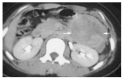

Results: Clinical presentation included a palpable abdominal mass in two patients and vague abdominal discomfort in another two. Two patients were asymptomatic; their tumors were found incidentally on abdominal sonographic examination for other reasons. The final patient was admitted with hemoperitoneum secondary to tumor rupture. The mean diameter of the tumors in the seven patients was 10.5 cm (range 5 to 20 cm). The lesions were located in the body and tail in five cases and in the head of the pancreas in two. Surgical procedures included distal pancreatectomy (3), distal pancreatectomy with splenectomy (2), pancreaticoduodenectomy (1) and a pylorus-preserving Whipple procedure (1). There were gross adhesions or histological evidence of infiltration to the adjacent pancreas and/or splenic capsule in four cases. None of the patients received adjuvant therapy. The mean follow up was 7 years (range 0.5 to 14 years). One patient developed multiple liver metastases after 14 years of follow up.